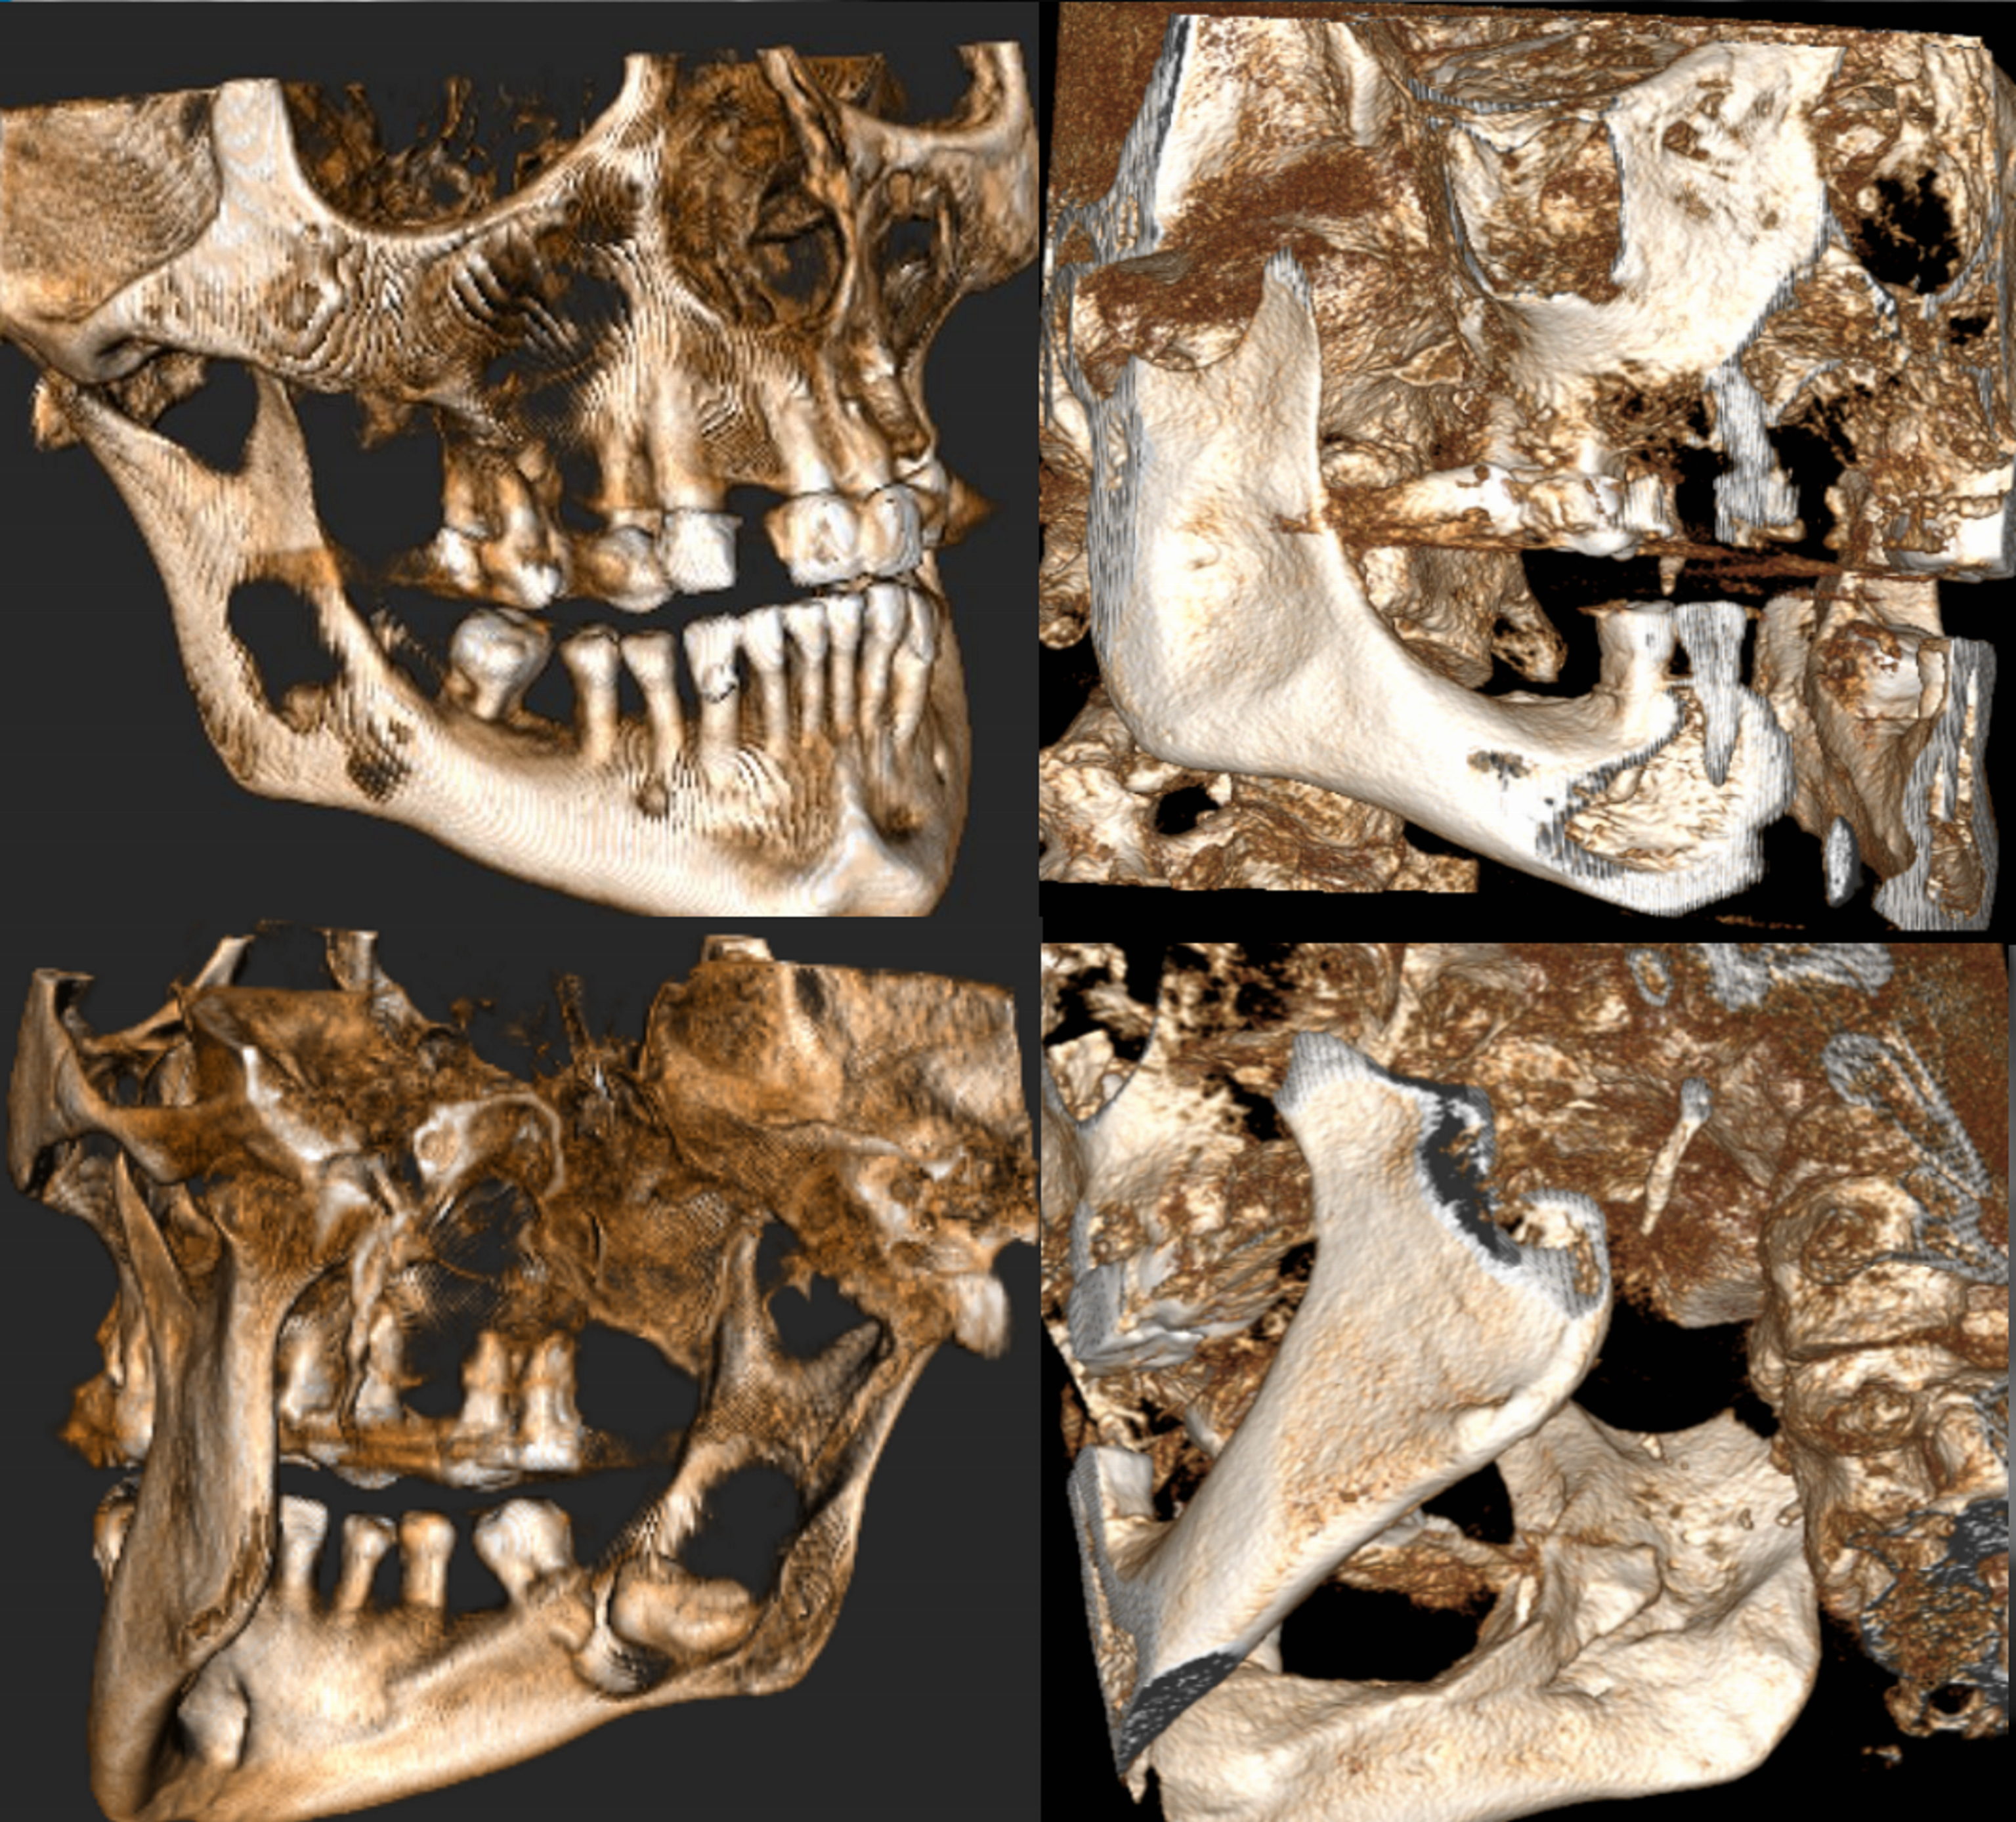

Pacjentka przyjmowała na stałe rywaroksaban i kwas acetylosalicylowy z powodu zakrzepicy żył głębokich kończyn dolnych oraz leki na nadciśnienie tętnicze – walsartan i amlodypinę. W badaniu zewnątrzustnym nie stwierdzono odchyleń od normy. W badaniu wewnątrzustnym stwierdzono chełbotanie wyczuwalne od strony przedsionkowej i językowej po stronie prawej żuchwy. W badaniu CBCT stwierdzono zmianę o charakterze osteolitycznym wielkości 43 mm × 41 mm × 12 mm (w największym wymiarze), która zajmowała prawy trzon, kąt i gałąź żuchwy oraz obejmowała drugi (ząb 47) oraz trzeci ząb trzonowy (ząb 48). Zmiana perforowała blaszkę zbitą od strony przedsionkowej i językowej (ryc. 1). Zaplanowano zabieg w znieczuleniu miejscowym. Dobę przed zabiegiem u pacjentki wdrożono antybiotykoterapię w postaci klindamycyny (300 mg), stosowanej co 8 godzin.

Ryc. 1. Badanie CBCT: a) rekonstrukcja pantomograficzna; b) przekrój poprzeczny; c) przekrój strzałkowy – widoczna zmiana o charakterze osteolizy, związana z zatrzymanym zębem 48 (listopad 2020).

Ryc. 4. Badanie CBCT, rekonstrukcje pseudotrójwymiarowe: po stronie lewej badanie przedzabiegowe (listopad 2020), po stronie prawej – badanie kontrolne po 1,5 roku od zabiegu (maj 2022).

Ryc. 5. Rekonstrukcje transsektalne: po stronie lewej badanie CBCT przedzabiegowe (listopad 2020), po stronie prawej badanie kontrolne po 1,5 roku od zabiegu (maj 2022) – pełne wygojenie kości.